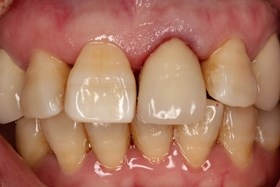

- 治療前全口X光片、口內正面照片。

治療前全口X光片、口內正面照片

假牙完成後,門牙特寫、切端特寫照,暴牙已不復見